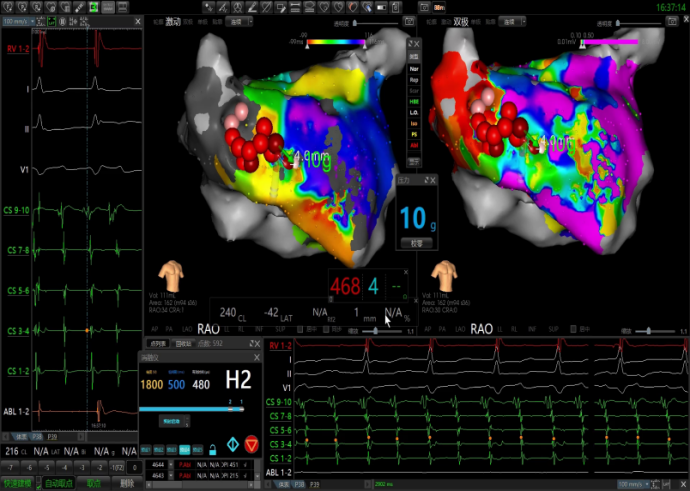

激动图显示为绕着前壁瘢痕区的折返,后壁为被动传导。

前壁瘢痕折返激动图

前壁消融:使用点状脉冲消融导管沿着瘢痕区域拉前壁线,最终将房扑打停,转为窦律。